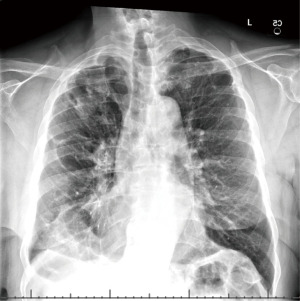

A 63-year-old man with GPB and a history of left-sided bullectomy in 1986 was lost to follow-up but presented in 2021 after a motor vehicle collision. On admission, he endorsed progressive dyspnea on exertion that predated the crash. CT scan demonstrated a giant bulla occupying >50% of the right thorax, causing ipsilateral atelectasis and contralateral tracheal shift (Figure 1). Also present was a right-sided pneumothorax and a left-sided hilar mass. The patient underwent inpatient bronchoscopy with biopsy of the hilar mass, which was negative for malignancy. His pneumothorax was managed with a chest tube, and he was discharged.

Over the next 1.5 years, the patient reduced his smoking and participated in pulmonary rehabilitation. His PFT at this time demonstrated moderately severe obstructive airway disease (Table 1). Repeat CT imaging showed minimal change in the size of his large bulla (Figure 2). The patient continued to follow up in clinic for another 8 months without a significant change in his imaging, PFT, oxygen requirement, or symptoms. He presented at this time for elective VATS bullectomy and wedge resection. His giant bulla was visualized to be located in the right upper lobe and occupied >50% of the hemithorax. This was removed and sent for pathology, which was consistent with lung parenchyma. The patient was also noted to have medium-sized bullae present in the right middle lobe. Two wedge resections were performed to remove this diseased tissue. The patient tolerated the procedure well. Two chest tubes were placed, which were removed three days post-operative (post-op). Follow-up chest X-ray two weeks later demonstrated expansion of the right lung without evidence of giant bullae or pneumothorax (Figure 3, Table 2).